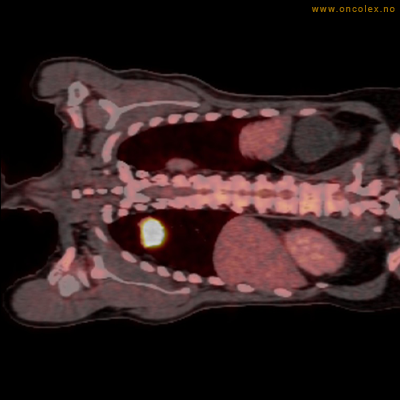

Vev som tar opp mer radioaktivt stoff, synes som hvite områder som lyser opp mer i forhold til annet vev som tar opp mindre sukker.

Høyt opptak av 18F-FDG ved analkreft.

Høyt opptak av 18F-FDG i adenokarsinom i rektosigmoideumovergangen. Fysiologisk opptak i blæren.